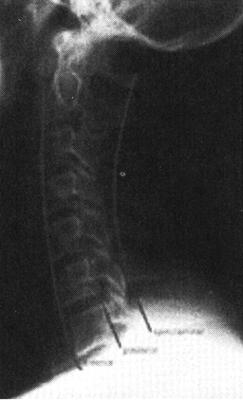

(一)X线平片和X线体层摄影

X线平片是脊柱损伤后的最基本和最重要的影像学检查方法,主要观察脊柱骨折和脱位情况。X线平片具有简单、易行和快速等优点,且可在不搬动疑似急性脊髓损伤患者的情况下在床边拍摄。X线平片空间分辨率高,骨骼结构成像清晰,目前仍是脊柱脊髓损伤检查的首选的影像学检查方法(图7-1)。临床上绝大多数的脊柱创伤骨折、关节脱位和半脱位都可通过普通X线的适当体位的投照而发现(图7-2)。脊柱常规投照位置有前后位、侧位和左、右斜位等。高质量的照片是诊断的最基本条件,如果一次照片不能满足诊断的需要,应调整相应的投照条件、胶片位置、球管中心以及投照角度重复拍摄,直至满意为止。对于怀疑有脊柱脊髓损伤患者应该在尽可能少搬动患者的情况下进行X线照片,尽量避免由于搬动病人而造成脊髓损伤加重。由于X线平片是投照部位解剖结构的重叠图像,限制了对复杂骨结构,特别是中轴骨骼解剖细节的显示,易漏诊细微而重要的骨折和错位。

图7-1 正常颈椎X线侧位片:正常颈椎前、中、后三柱连线光滑连续,中、后柱连线之间为脊髓所在

图7-2 C5以上前脱位,中、后柱连线显示在C5水平处明显狭窄,表明颈髓在此处受压